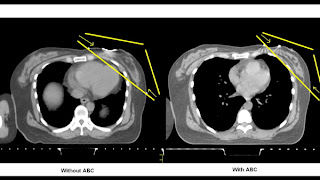

Women with cancer on the left side, who also require radiation, are at higher risk for heart trouble down the road. The proximity of the heart to the breast makes it a target for complications. That’s why Sunnybrook is increasingly using a technique called Active Breathing Control, or ABC. Eligible patients simply hold their breath during treatment with the help of special equipment. Over time and with practice, it becomes easier for many women and gives them a powerful tool to protect their heart health while fighting cancer.

| A comparison of two heart images: without ABC (left) and with ABC (right). |